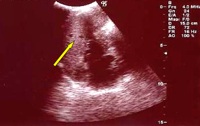

Si decide di eseguire l�ecografia addominale che a livello della milza evidenzia plurime e diffuse piccole zone ipoecogene (Figura 2). All'ilo epatico e in sede periportale evidenza di alcuni linfonodi ovalari, con diametro compreso entro 2 cm. Nella norma il parenchima epatico.

Figura 2. Ecografia Splenica. Milza con ecostruttura disomogenea per la presenza di plurime e diffuse areole nodulari ipoecogene, del diametro compreso tra 8 e 15 mm di non univoca interpretazione (foci flogistici?).